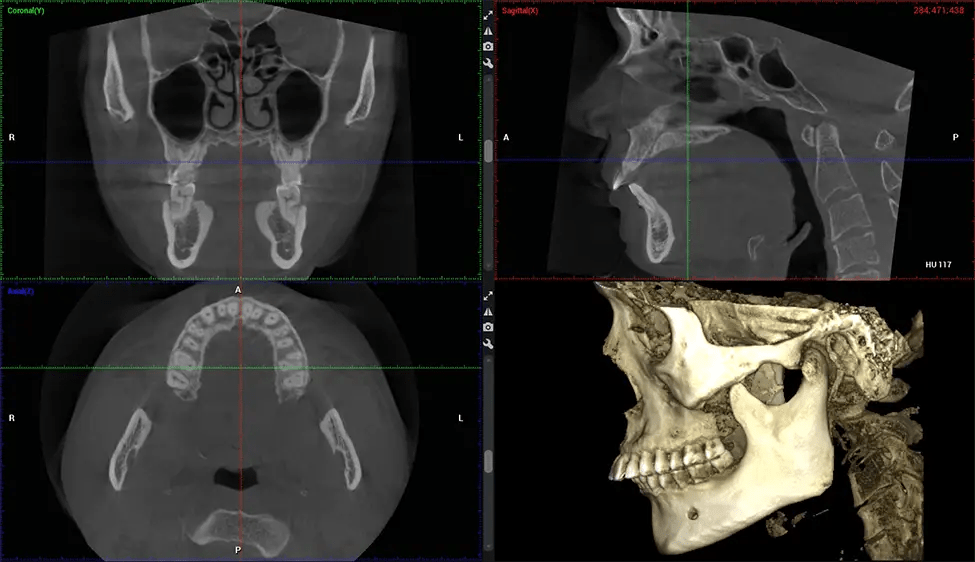

Full Skull to C7 of the Spine

Upper Cervical Chiropractor Diagnosing structural problems in the C1-C2 vertebrae, assessing misalignment and instability, and evaluating chronic pain. Enables precise, weight-bearing views of the upper cervical spine, helping to identify abnormalities that inform targeted, non-invasive therapies.

Planmeca Viso G7 CBCT ( Cone Beam CT Scan ) is designed to surpass the demands of industry leaders, specialists, and large institutions. It’s has a large ø25×30 cm sensor with four built-in cameras. It can capture unlimited volume sizes from a ø3×3 cm to a ø30x30cm volume capturing the skullcap through C7 on the cervical spine. The Planmeca Viso G7 offers the industry’s largest single volume scan of ø30×19 cm. It’s poised to handle advanced imaging modalities such as Planmeca ProFace® and Planmeca 4D™ Jaw Motion technology. The occipital head support allows an unimpeded view of facial tissue.